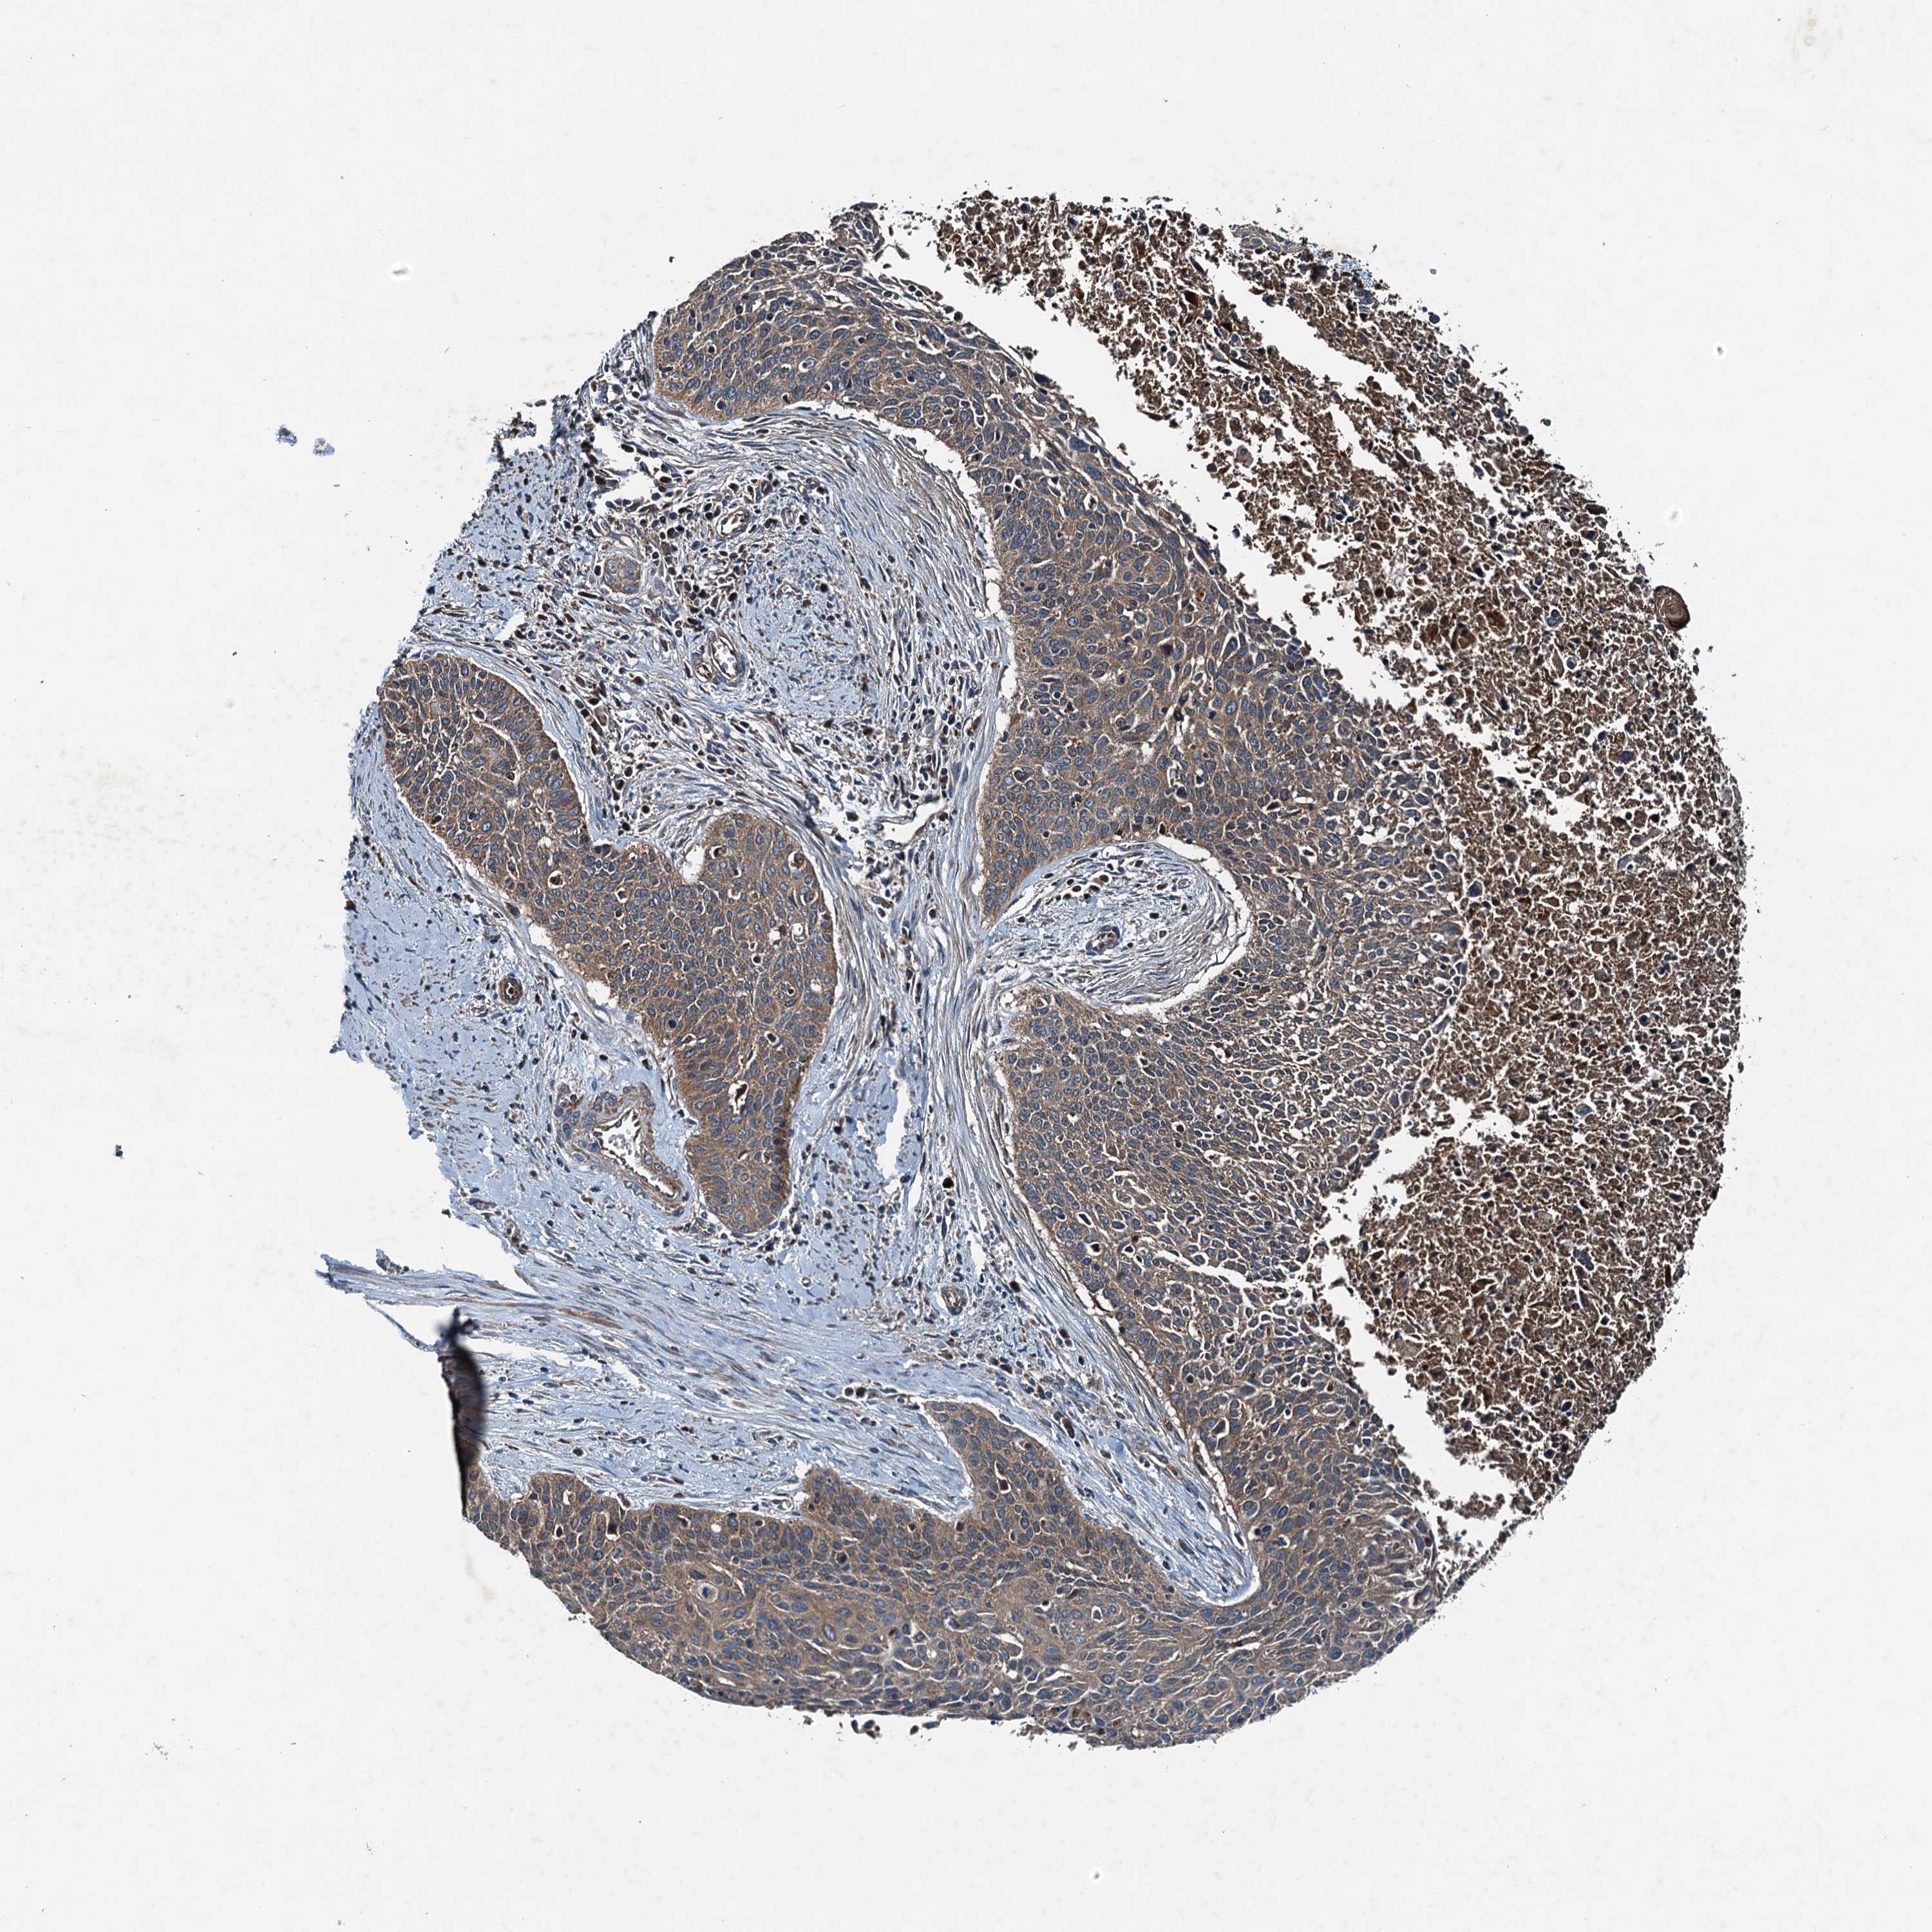

CERVICAL CANCER - Protein expressioni

A mouse-over function shows sample information and annotation data. Click on an image to view it in a full screen mode. Samples can be filtered based on level of antibody staining by selecting one or several of the following categories: high, medium, low and not detected. The assay and annotation is described here.

Note that samples used for immunohistochemistry by the Human Protein Atlas do not correspond to samples in the TCGA dataset.

Antibody stainingi

Antibody staining in the annotated cell types in the current human tissue is reported as not detected, low, medium, or high, based on conventional immunohistochemistry profiling in selected tissues. This score is based on the combination of the staining intensity and fraction of stained cells.

Each image is clickable and will lead to virtual microscopy that enables deeper exploration of all samples and also displays staining intensity scores, fraction scores and subcellular localization as well as patient and tissue information for each sample.

Antibody HPA041227

Staining

High

Medium

Low

Not detected

Intensity

Strong

Moderate

Weak

Negative

Quantity

>75%

75%-25%

<25%

None

Location

Nuclear

Cytoplasmic/membranous

Cytoplasmic/membranous,nuclear

Squamous cell carcinoma, NOS

Adenocarcinoma, NOS